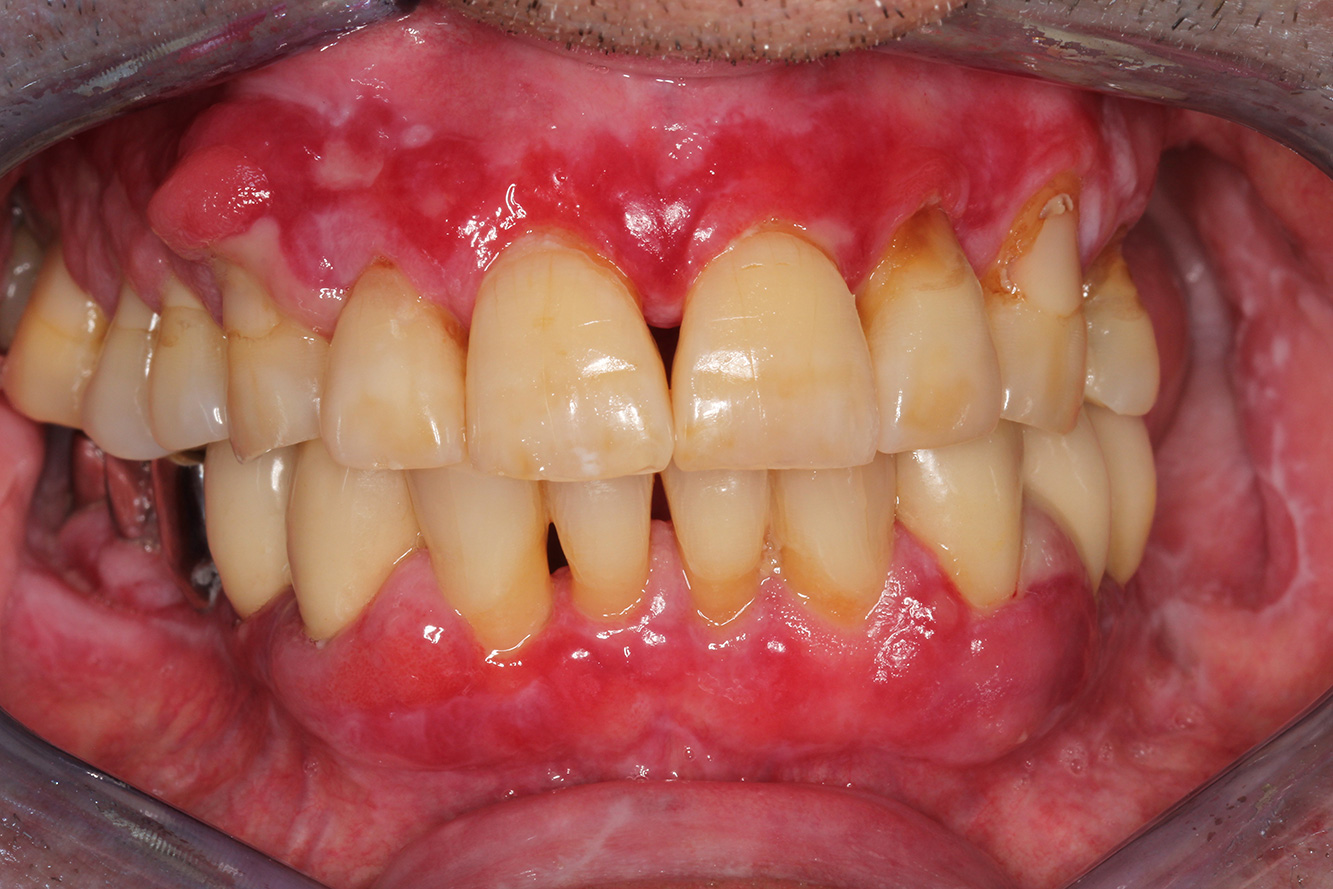

Pacient sănătos cu boală parodontală incipientă

Pacientul în vârstă de 68 de ani nu are nicio afecțiune generală și nu ia niciun medicament care ar putea fi relevant pentru sănătatea sa orală, iar stilul său de viață nu prezintă niciun risc special. Pacientul are două implanturi dentare (cadranul 3, de cinci ani) și un caz anterior de boală parodontală (stadiul IV, gradul B) cu pierderea dinților. În prezent, condițiile parodontale sunt stabile. Cu toate acestea, parodontoza crește semnificativ complicațiile biologice ale implanturilor și există riscul de pierdere a implanturilor (21). Se pot determina patru recomandări pentru ședința de profilaxie. mai multe

NIWOP – No Implantology without Periodontology